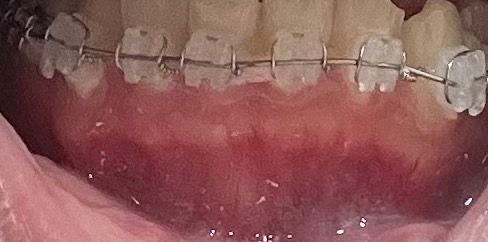

치아 교정 아랫니 잇몸뼈가 튀어나오는 것 같아요

치아교정 3일차인데 교정 전에는 이렇게 잇몸뼈가 막 튀어나와 보이지 않았는데 교정 하면서 점점 튀어나와 보여요.. 실제로 보면 좀 더 심한데 괜찮은 걸까요?

아랫니만 이래요

• 1번 째 사진